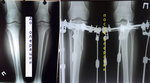

ножки в аппаратах, в день снятия.

Отправляю вам контрольные рентген-снимки и фото ножек. Со дня снятия прошло 50 дней.

Здравствуйте, Наталья! По рентгену, всё отлично! разрешено всё без ограничений! Исключить: беременность в течении первых 6 месяцев.